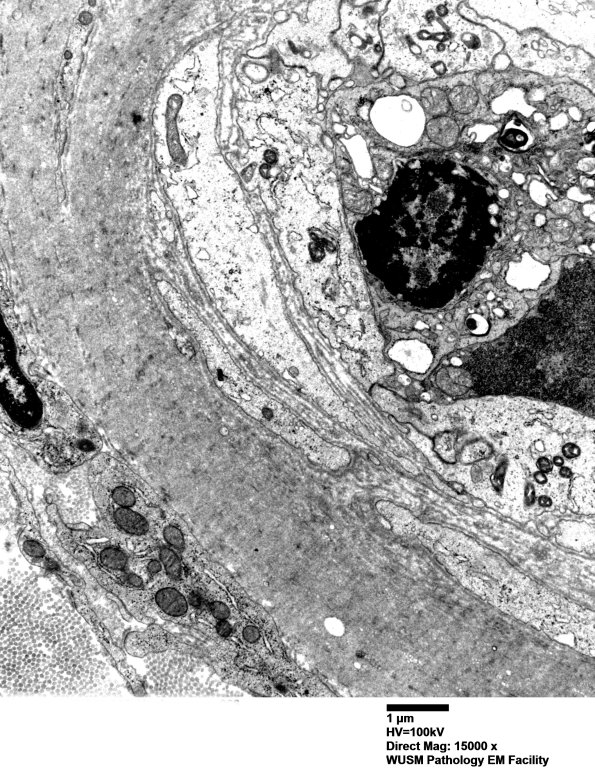

Washington University Experience | VASCULAR | Hypoxia-Ischemia, fetal-neonatal | White Matter | 5C5 (Case 5) EM066 - Copy

5C5 (Case 5) EM066 - Copy